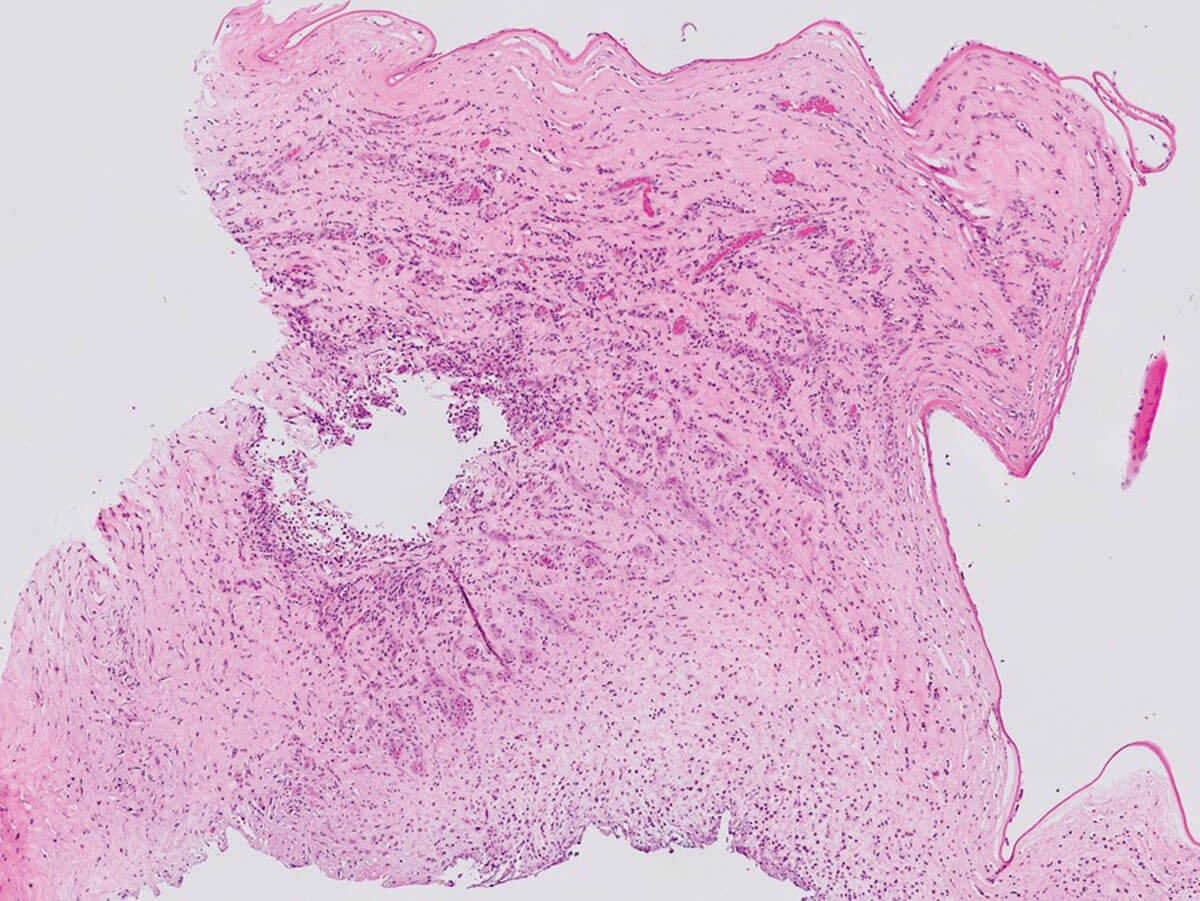

Figure 2a: H&E x20.

- What do Figures 2a and 2b show?

1. Severe acute keratitis with severe ulceration, complete sloughing of the epithelium and loss of Bowman’s layer. Some viable cornea remains. Figure 2b shows thin fungal septate hyphae with 45° branching (Y-shaped), favouring Aspergillus species.

Acanthamoeba cysts can usually be seen on H&E and on special stains (Giemsa). Fungal hyphae and spores can also be easily highlighted by special stains (DPAS, in this case). Fungal elements are often found deep in the ulcer bed or in the adjacent viable stroma.

Fusarium and Aspergillus species (filamentous fungi more common found in warmer climates) and Candida (a yeast more common in cooler climates) are the most common pathogens. Although much more common in tropical climates, the incidence is increasing in the UK and the diagnosis should be considered when the ulcer does not respond to or progresses after initial antibiotic treatment. Microscopic features are common to fungal and bacterial infections: epithelial destruction / ulceration, necrosis, neutrophilic infiltration, stromal oedema and neovascularisation, and discontinuities of the Descemet membrane. If fungal organisms can be visualised typing according to their morphology is usually possible.